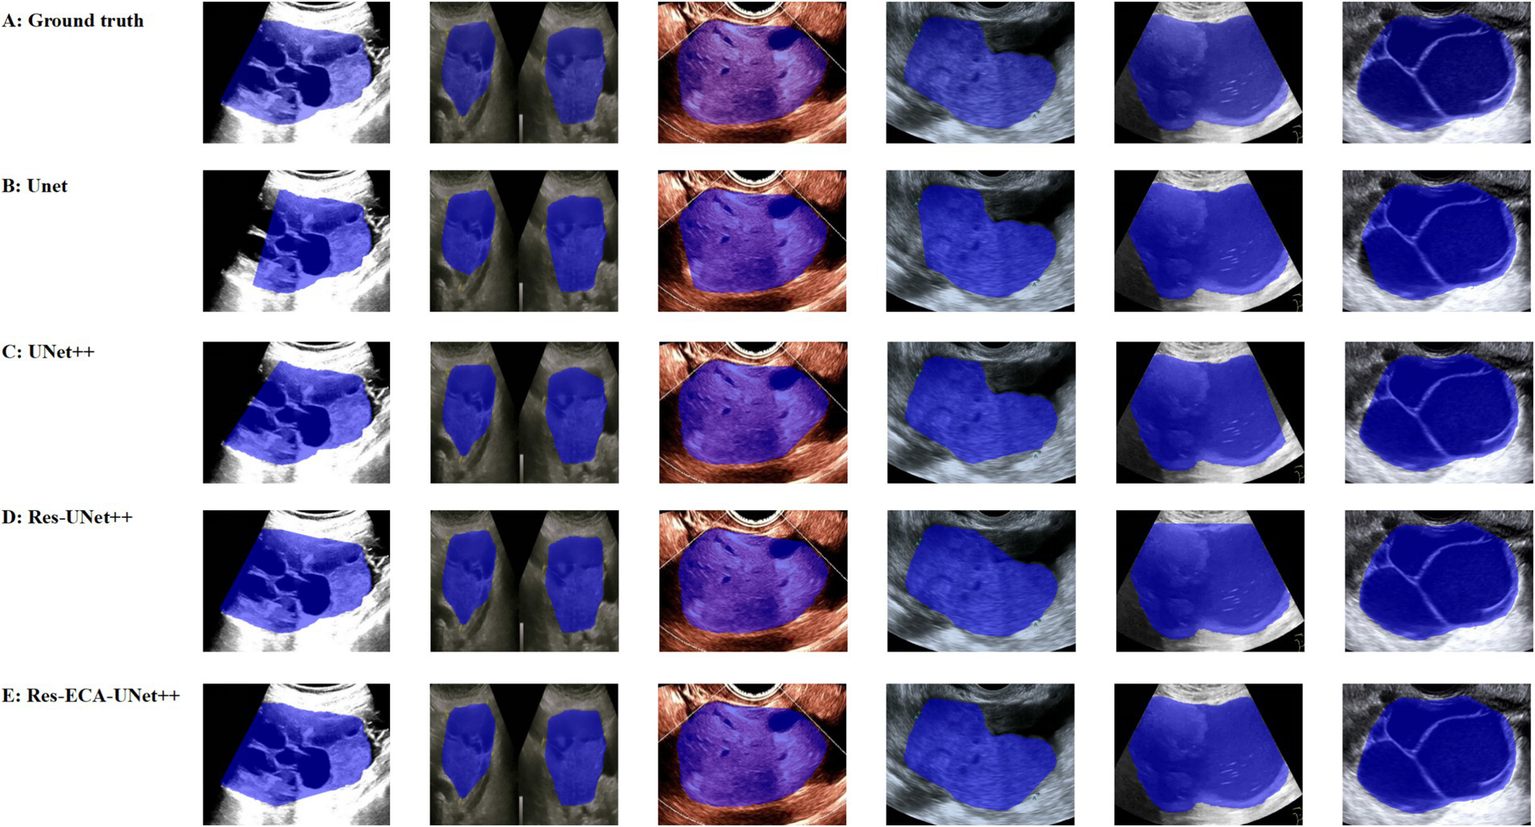

While the improved model demonstrates enhanced accuracy in tumor region segmentation, we conducted a visual comparative analysis using representative ovarian cases from our proprietary dataset to further elucidate performance differences across various lesion types. As illustrated in Figure 7, when processing lesions with irregular tumor boundaries, although U-Net series models achieve adequate coverage of major tumor regions, their edge delineation appears coarser with unstable fitting characteristics, particularly showing boundary displacement in low-contrast regions. In comparison, Res-ECA-UNet++ exhibits superior performance in handling most lesion types, though minor boundary deviations persist when processing complex marginal details, indicating potential for improvement in precisely modeling irregular-edged lesions.

Figure 7

Visual comparison of segmentation results from different models.

Furthermore, the models demonstrate a tendency for over-segmentation when encountering background interference or ambiguous boundary regions, suggesting insufficient structural representation capability at lesion margins. Particularly in areas with regular contours and homogeneous echogenicity, boundary fitting errors reveal the models’ limited robustness in handling transitional boundary ambiguity. Despite Res-ECA-UNet++'s exceptional performance in large lesion identification and boundary precision, optimization potential remains for processing indistinct-bordered lesion types. Future research directions may consider implementing multi-scale modeling mechanisms or boundary enhancement modules to improve the model’s adaptability and robustness when handling highly variable targets.